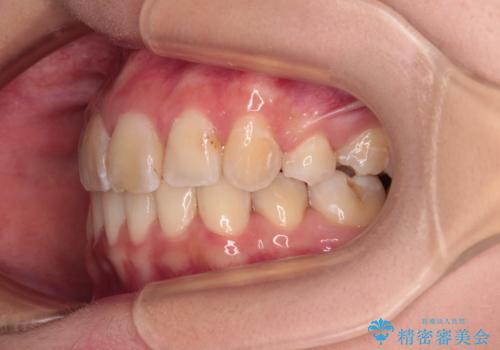

デコボコと深い咬み合わせ ワイヤー装置での抜歯矯正

- 内側に倒れ込んだ歯や下の前歯が隠れてしまうほどの咬み合わせを改善したいとのことで来院された患者様です。

下顎の叢生を解消するために抜歯が必要であり、奥歯の咬み合わせや口元の印象から、上顎も同様に抜歯と判断し、上下左右の第1小臼歯4本抜歯してワイヤー装置にて矯正治療を行うこととしました。

咬み合わせが深く、そのままでは上顎の抜歯スペースが閉じきらない可能性があったため、治療初期から深い咬み合わせを改善させるように試みました。

実際にはなかなか改善されず、当初予定よりも治療期間がやや長期化してしまいました。